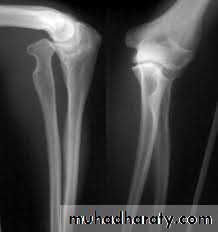

CONGENITAL DISLOCATION OF THE RADIAL HEAusually dorsal dislocations, the radial head present as a lump on the lateral side of the elbow. It become dome shaped dueto unrestrained growth.